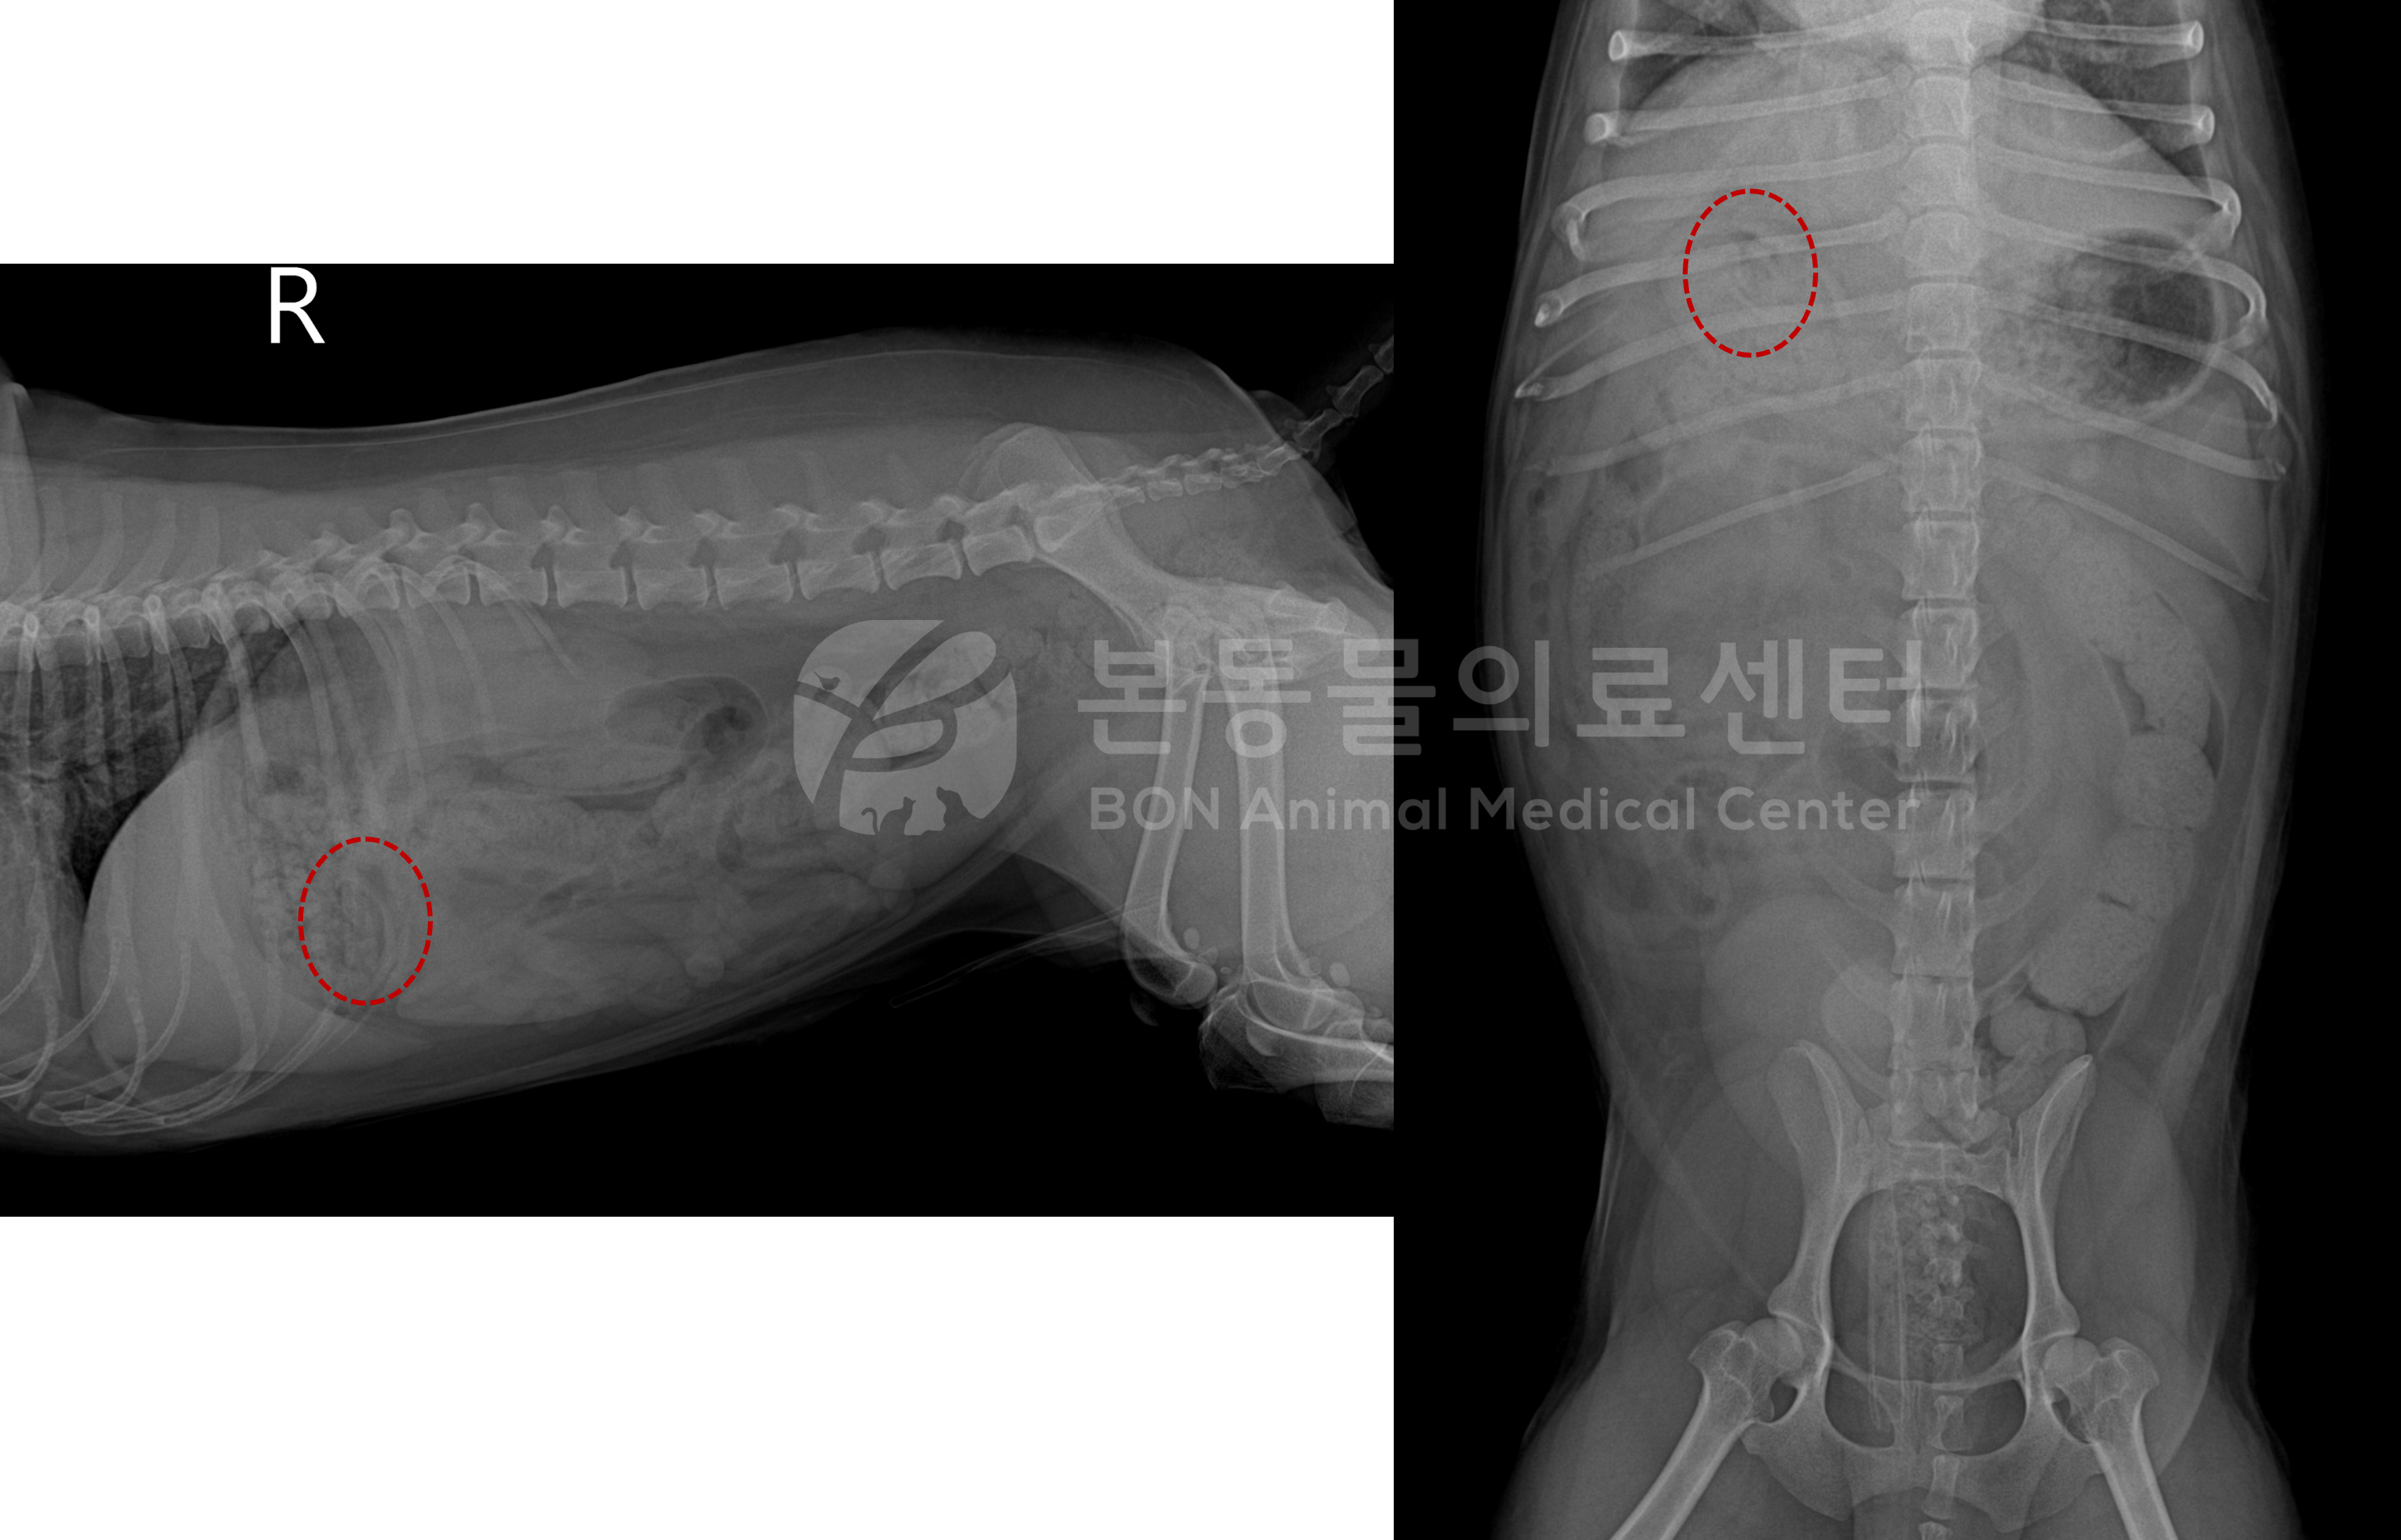

복부 방사선 검사(빨간 점선 : 씨앗 의심 이물)

먼저, 씨앗의 위치를 확인하기 위해 영상 검사를 진행하였다.

복부 방사선 사진 상 점선처럼 씨앗 의심 구조가 확인되고, 초음파 검사 시 형태 (curved-linear structure) 등을 고려 시 위 내 씨앗 이물이 저류된 것으로 강하게 의심되어 우선 구토 처치를 실시하였다.